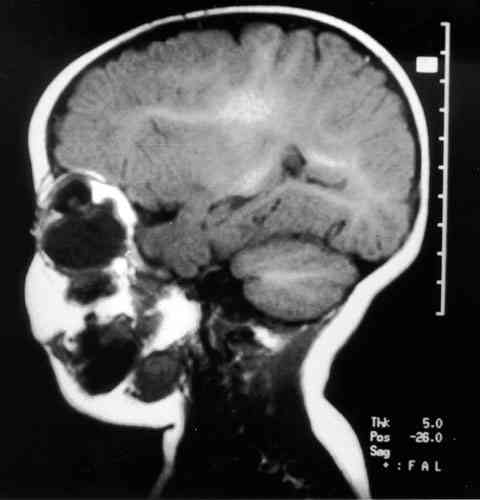

Figura 1

RESONANCIA NUCLEAR MAGNÉTICA EN T1, CORTE SAGITAL ÓRBITA DERECHA, DONDE PODEMOS OBSERVAR TUMORACIÓN INTRAORBITARIA QUÍSTICA EN ÍNTIMO CONTACTO CON EL GLOBO OCULAR. EL CONTENIDO QUÍSTICO PARECE DE DENSIDAD SIMILAR AL LCR.